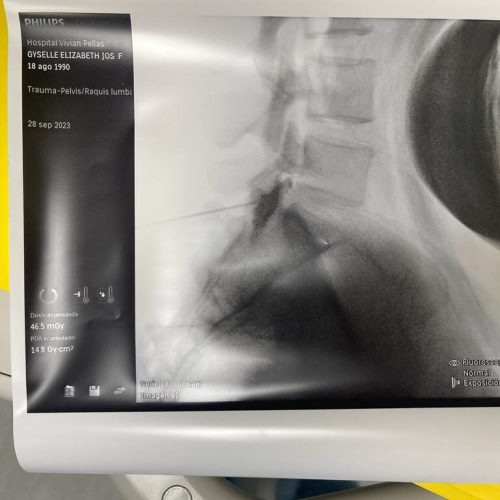

3. Rizólisis (Ablación por radiofrecuencia)

¿Qué es?

Procedimiento no invasivo que utiliza radiofrecuencia para desactivar nervios que transmiten dolor crónico en la columna.

Rizólisis (Ablación por Radiofrecuencia)

Técnica mínimamente invasiva para tratar el dolor crónico articular de la columna

La rizólisis es un procedimiento no quirúrgico que utiliza energía de radiofrecuencia para inactivar de forma selectiva los nervios responsables de transmitir dolor desde las articulaciones facetarias de la columna.